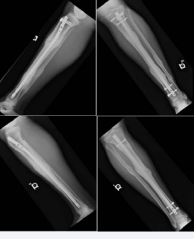

Figure 3: Anterior-Posterior and Lateral initial radiographs of a 49 year-old male who sustained bilateral segmental tibia fractures as a pedestrian stuck by a motor vehicle, which underwent placement of a Tibial intramedullary nail. Repeat radiographs at 13 months s/p injury demonstrate abundant callous and bony union of the fracture sites.